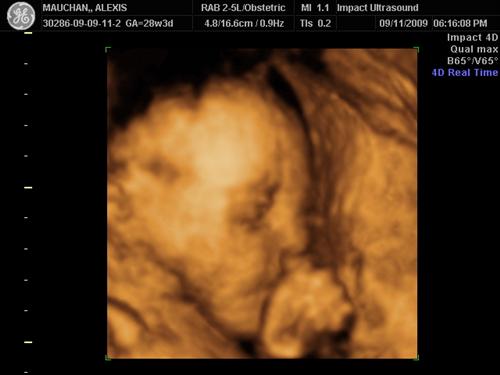

28 Weeks